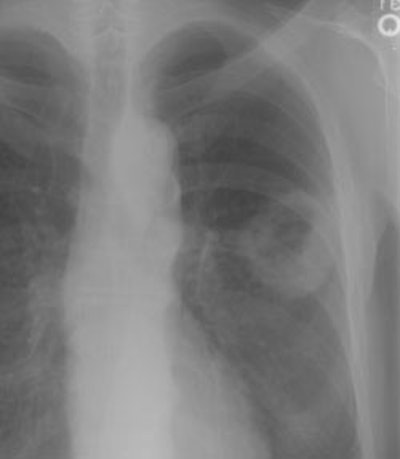

New Criterion for Determination of Pathologic Hilar Adenopathy

Example 1: This is an example of an N1 node in a patient with a lingular adenocarcinoma (left image). Although not pathologic by short axis size criteria, the lymphatic tissue in the left hilum has a convex border with the adjacent lung (white arrows). This node contained adenocarcinoma at histopathologic analysis. Some authors advocate using the presence of a convex margin of the interstitium with the lung parenchyma to indicate pathologic adenopathy to improve the sensitivity of CT for detecting hilar metastases [36].

Example 2: This patient is an example of a false negative CT for hilar nodal metastases even when applying the suggested new criterion. The patient had a peripheral adenocarcinoma in the left upper lobe (black arrows). The left hilar node (yellow arrows) is not pathologic by size criteria, nor does it exhibit a convex margin with the adjacent lung parenchyma. This is a normal node by CT, however, at histopathologic analysis the node was positive for malignant cells.